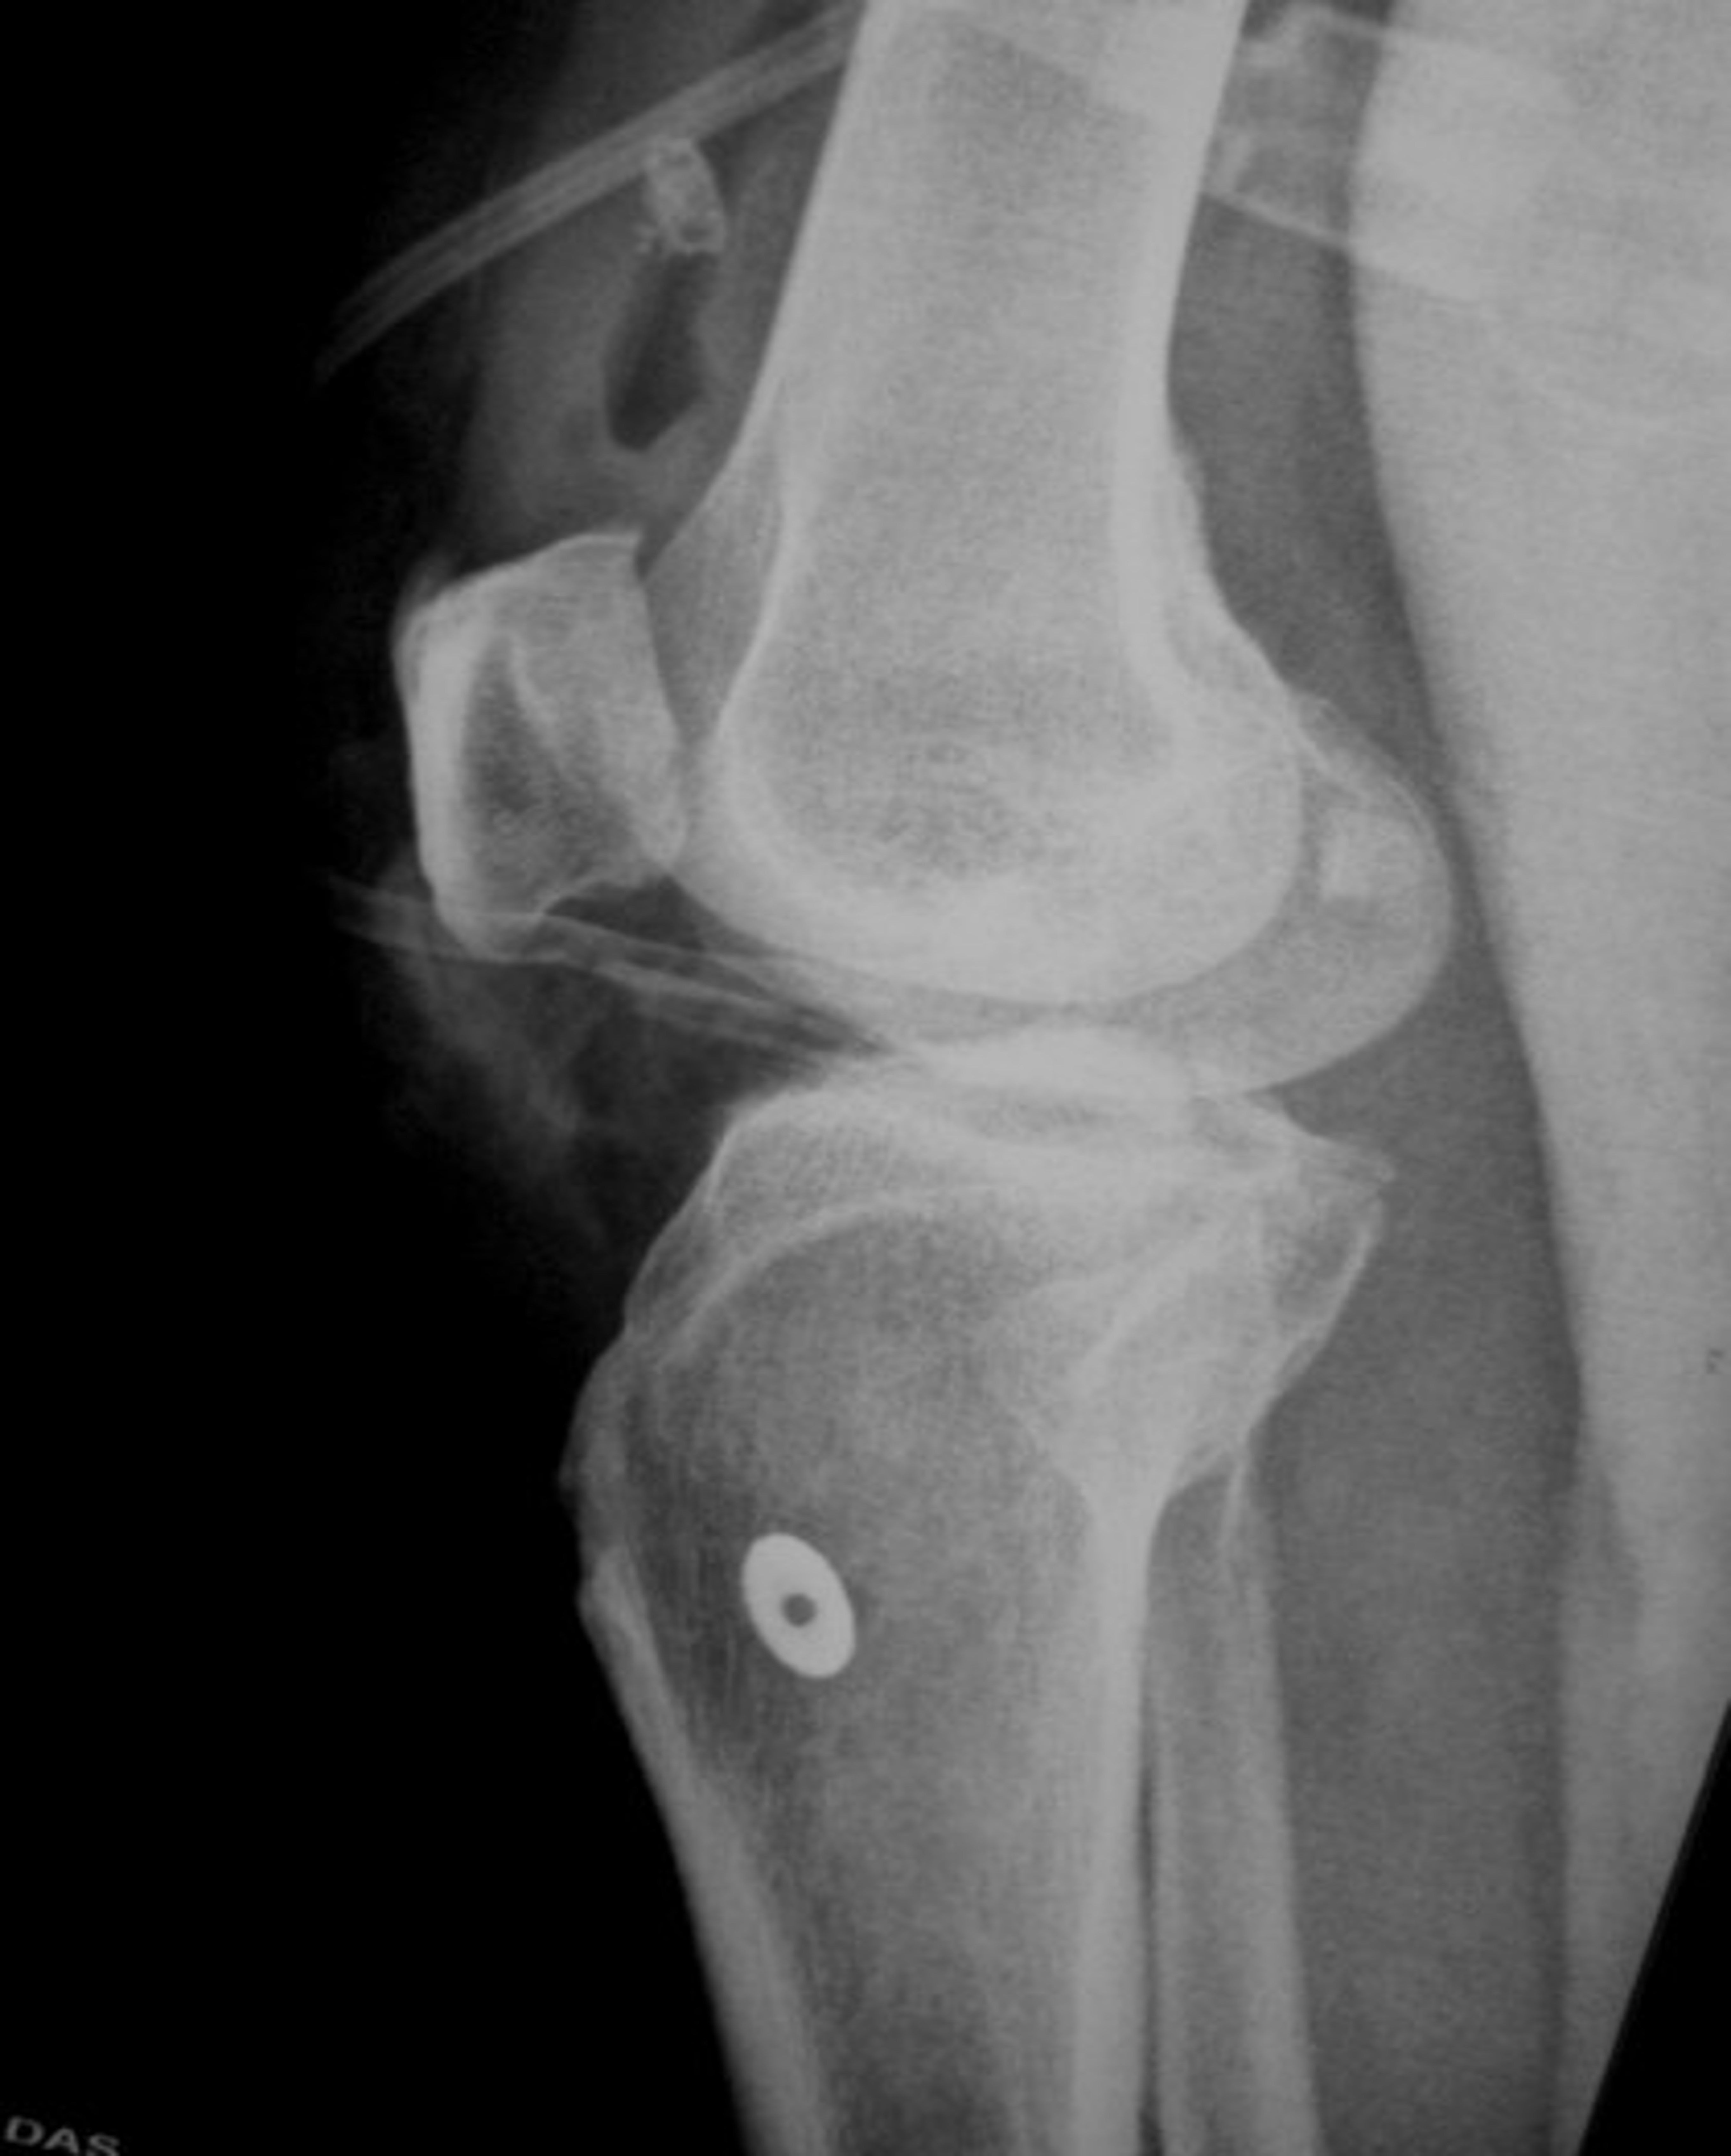

Case 1 pre op xrays and post op xrays